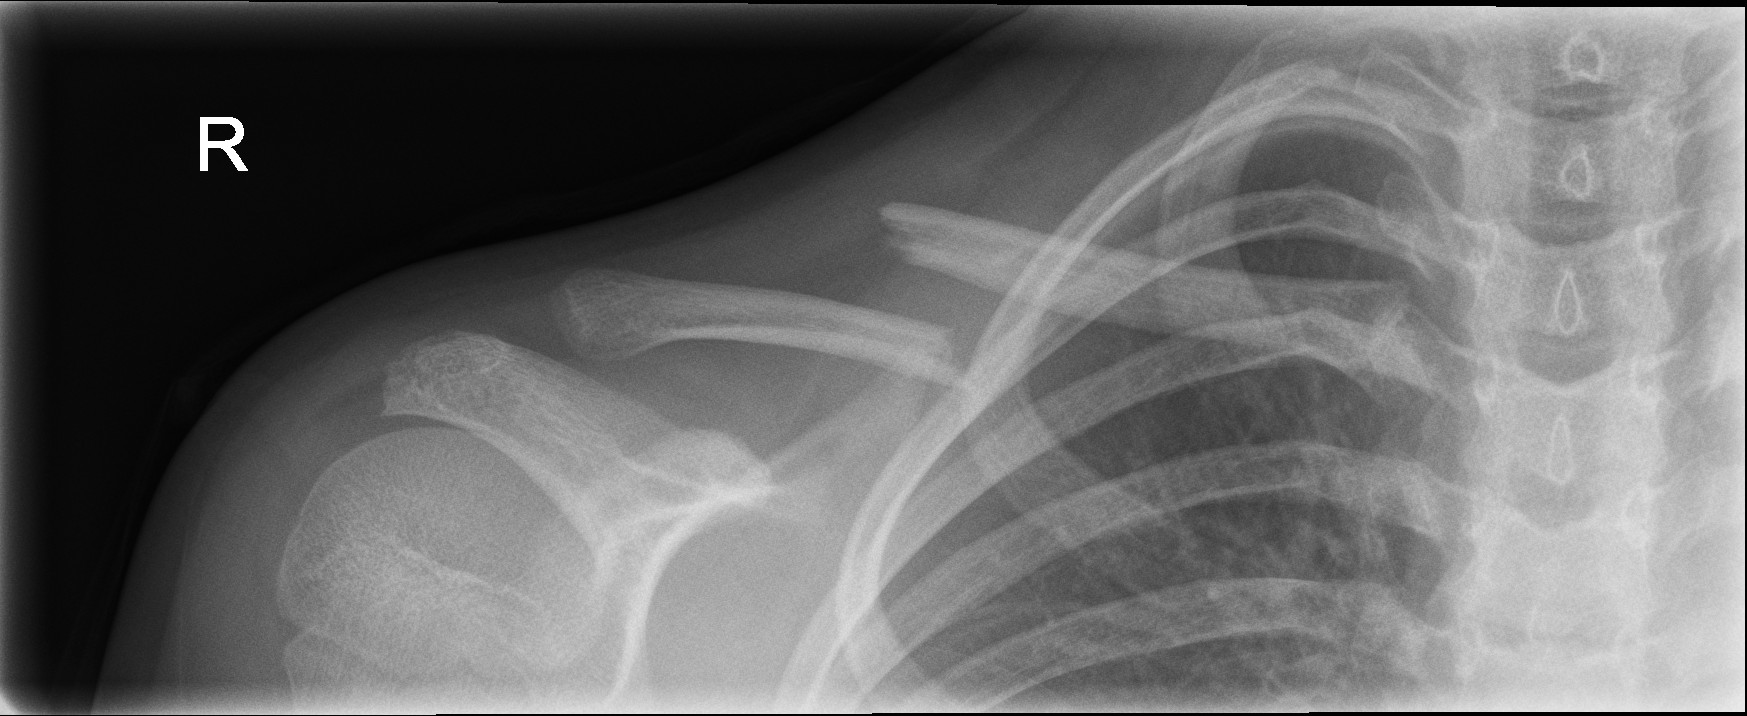

Significantly displaced middle third fractures

Displaced middle third clavicle fracture